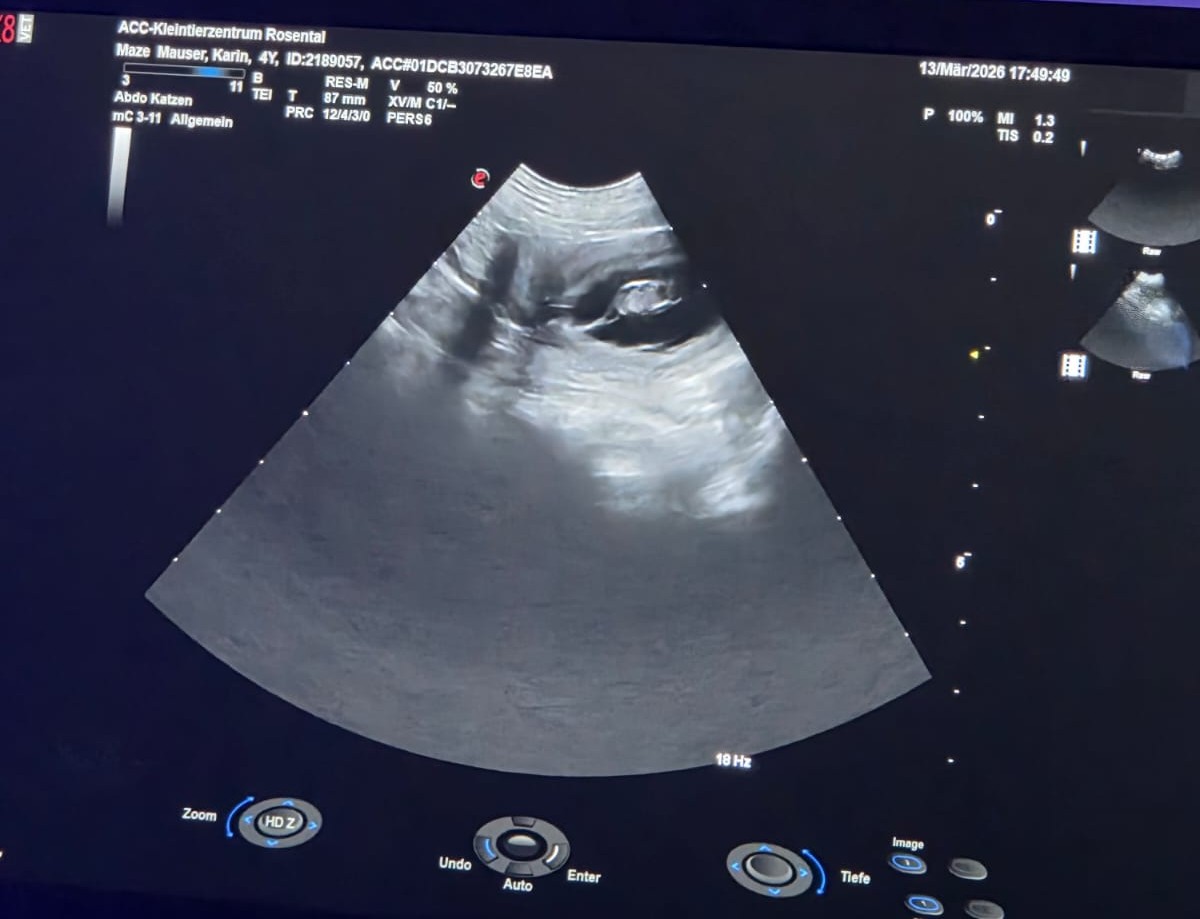

Am

13.3.2026 war es endlich so weit - der langersehnte Ultraschalltermin.

Und Freitag der 13. hat uns Glück gebracht! Wir konnten mehrere

Fruchtanlagen sehen und freuen uns sehr!